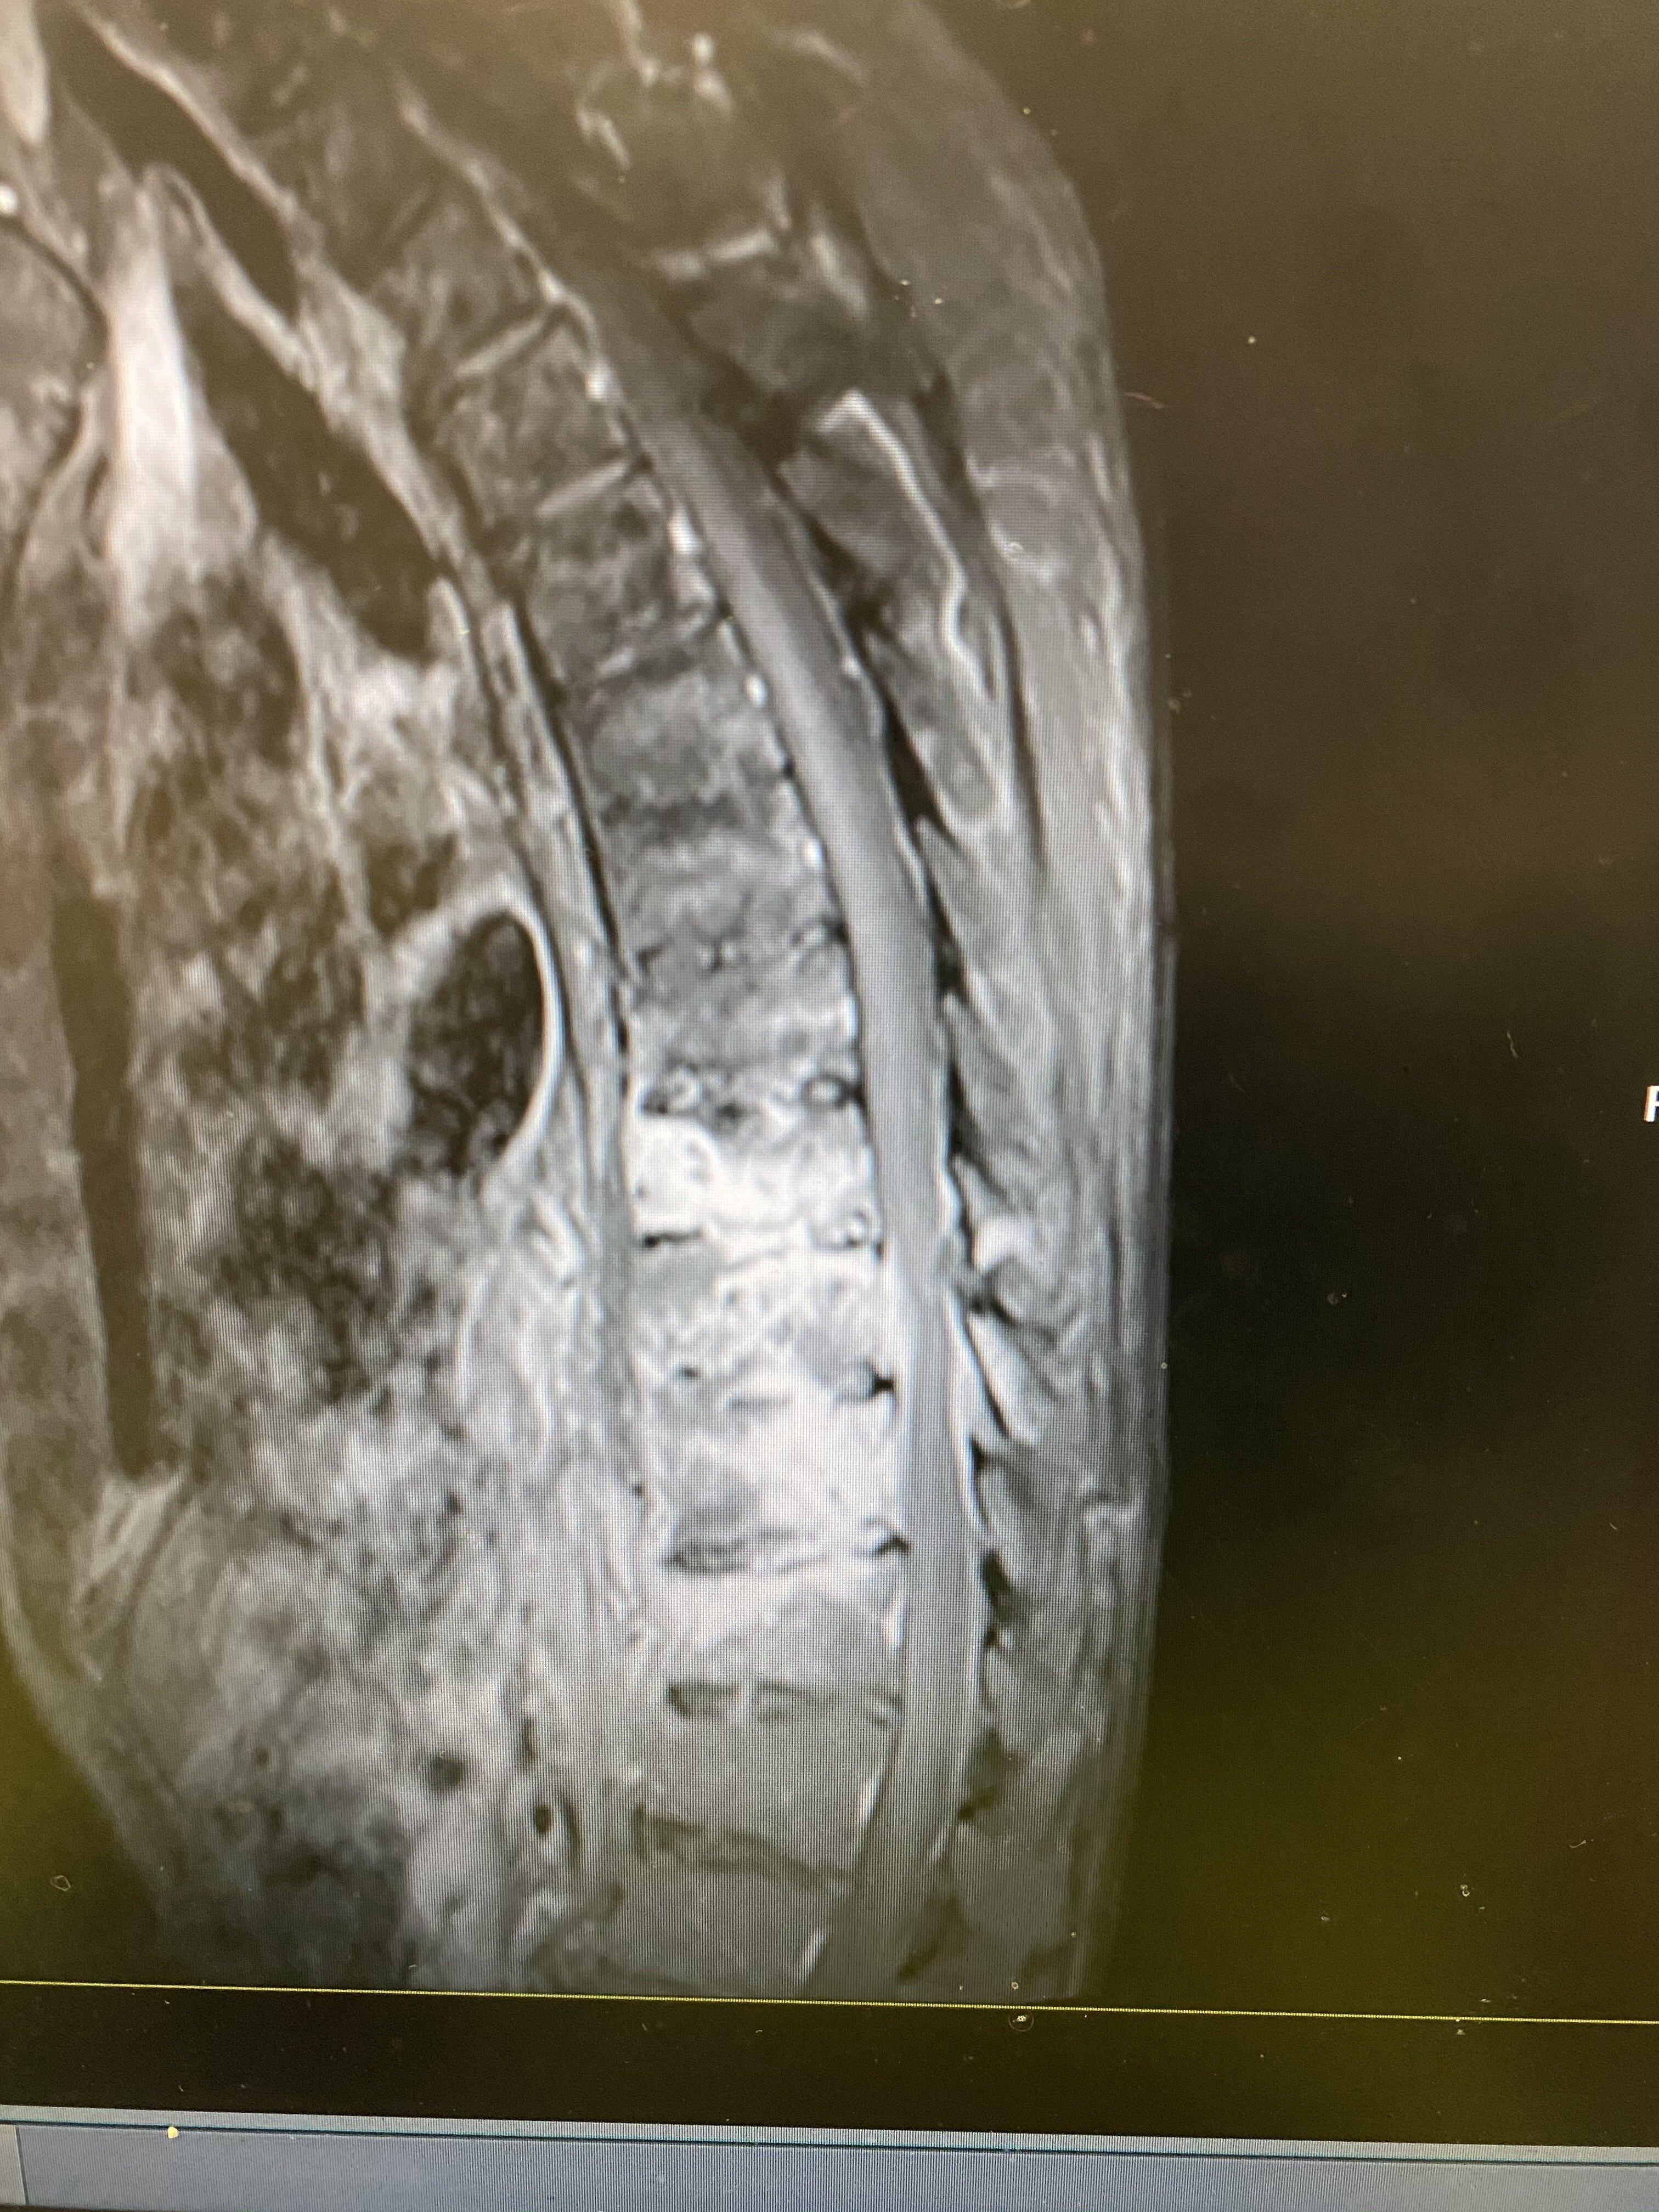

该患者老年男性,肺结核,低热乏力行抗结核治疗两个月以后,持续胸痛、背痛,无法缓解。做胸椎核磁共振和CT考虑胸椎结核,椎体椎间盘结合病灶,椎旁脓肿形成,椎体破坏明显。